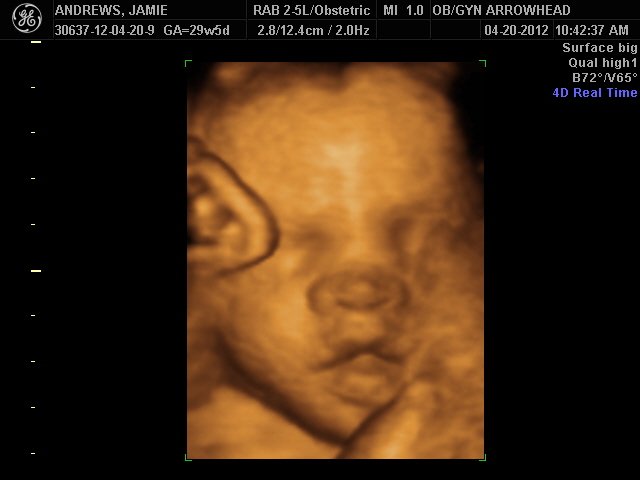

We offer complimentary 3D/4D Ultrasounds to all our OB patients around 30 weeks! The following photos are some examples of our work, shown with permission from our patients.